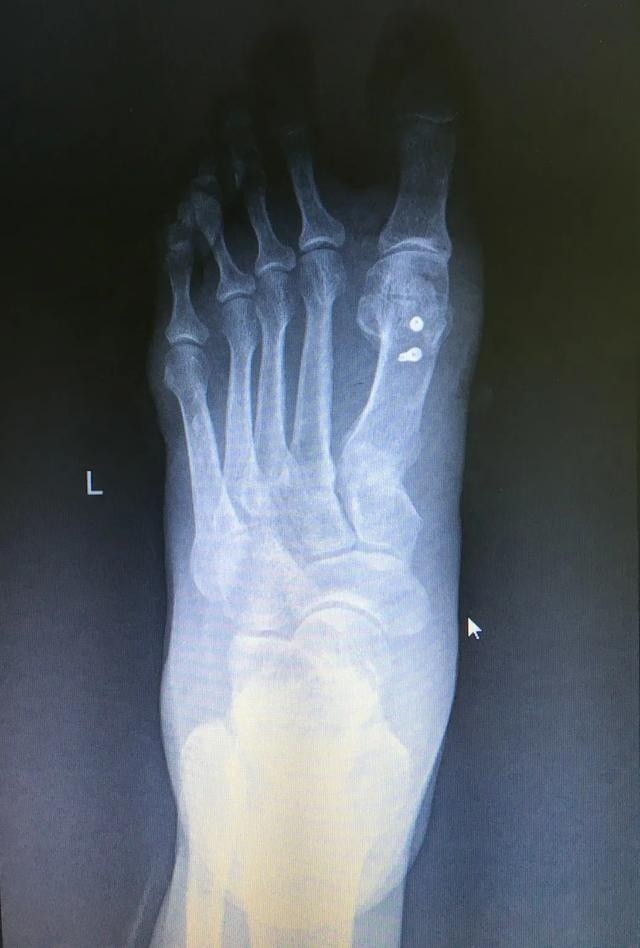

踇外翻 大脚骨

图片尺寸1080x1920